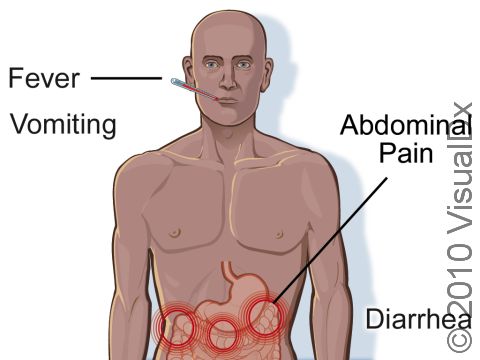

Gastrointestinal Anthrax

- Fever

- Nausea

- Decreased appetite

- Diarrhea, usually bloody

- Abdominal pain